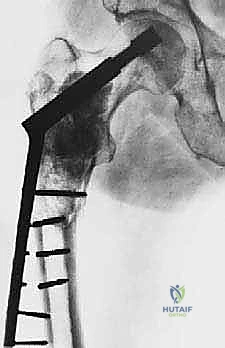

- اختيار نوع المفصل الاصطناعي: بناءً على صور الأشعة المقطعية، يحدد الجراح نوع المفصل. في حالات الأورام، غالباً ما تُستخدم مفاصل ذات جذوع طويلة (Long-stem prostheses) لتجاوز منطقة الورم وتثبيت المفصل في العظم السليم أسفل الآفة. كما تُستخدم تقنية الأسمنت العظمي (Bone Cement - PMMA) بكثافة لتوفير استقرار فوري للمفصل والسماح للمريض بالمشي في اليوم التالي.

الخطوة 4: تحضير عظم الفخذ وتثبيت الجذع (Femoral Stem Insertion)

- يتم تجويف القناة النخاعية داخل عظم الفخذ لتتناسب مع حجم الجذع المعدني (Stem).

- في مرضى السرطان النقيلي، يُفضل استخدام الأسمنت العظمي لتثبيت الجذع. الأسمنت العظمي لا يعمل كصمغ فقط، بل كحشوة تملأ الفراغات التي تركها الورم وتوفر دعماً ميكانيكياً فورياً.

- يتم وضع رأس معدني أو خزفي (Ceramic Head) على قمة الجذع.